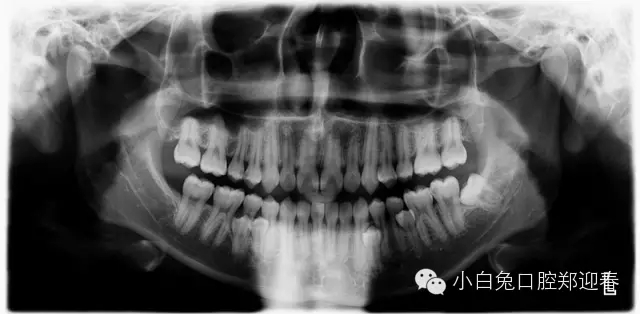

“多生牙”案例集錦(鄭穎春)......

額外牙可發(fā)生于乳牙列,也可發(fā)生于恒牙列,但恒牙列發(fā)生率多于乳牙列。額外牙經(jīng)常在上頜出現(xiàn),上、下頜出現(xiàn)比例為10∶1,可單個(gè)或多個(gè)、單側(cè)或雙側(cè)出現(xiàn),形態(tài)可同正常牙,也可是畸形牙、過(guò)小牙。